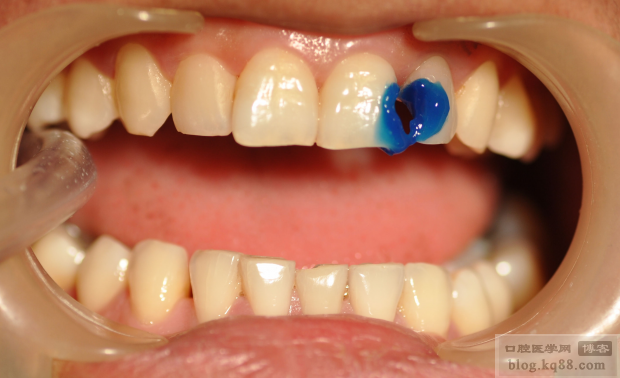

外形恢復(fù)后,制作硅膠導板

硅膠導板完成后,酸蝕牙齒

在硅膠導板上制作背板

背板完成